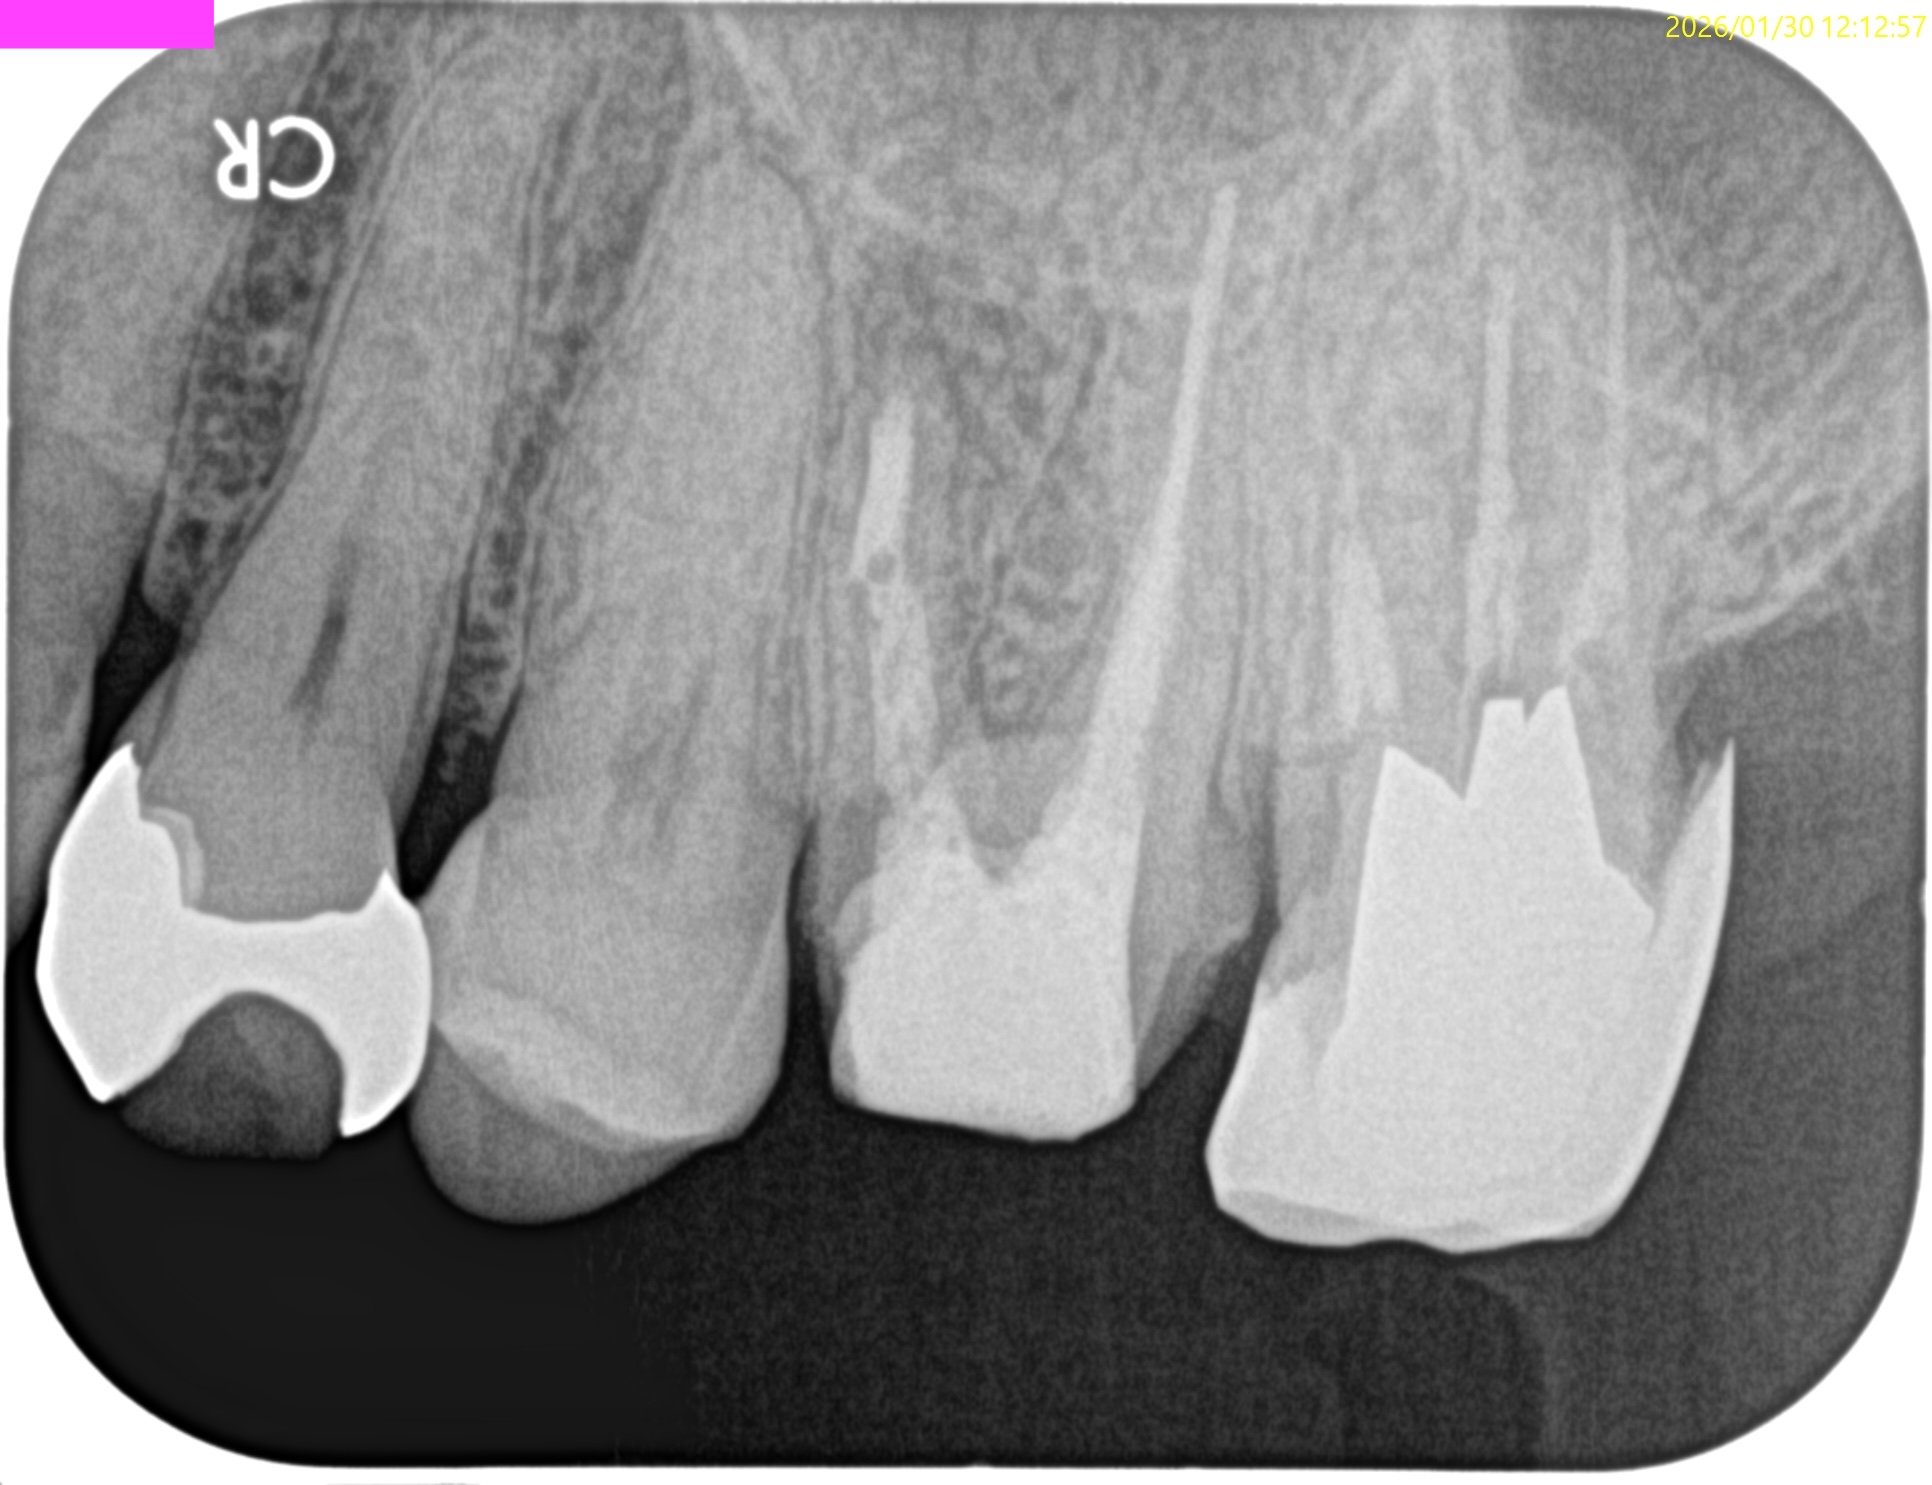

Pre-op Endo Test(2026.1.15)

#14 の頬側には8mmの歯周ポケットがあった。

これが割れていると言われている所以の一つである。

画像はどうだろうか?

MBの歯根周囲に病変がある。

MBの根管口部もいかにもピーソーリーマーで掘りましたよ、とVRFを惹起させる可能性が高い状況証拠まで存在する。

そしてそこに歯周ポケットが8mm…

VRFが濃厚かもしれない。